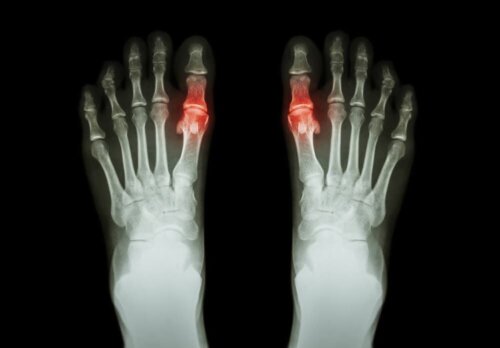

Gigt har tendens til at forekomme i form af smerte og vanskeligheder med at bevæge det eller de berørte led. I nogle tilfælde involverer det også stivhed og hævelse i samme område. Det påvirker måske et eller flere led på samme tid. Det kan også være symmetrisk eller asymmetrisk.

Hver type har sine særlige forhold, og den tid, symptomerne kan vare, er varierende. For eksempel er leddegigt en symmetrisk type gigt, der påvirker små led såsom fingrene. Urinsyregigt er på den anden side en type gigt, der har tendens til kun at påvirke ét led.